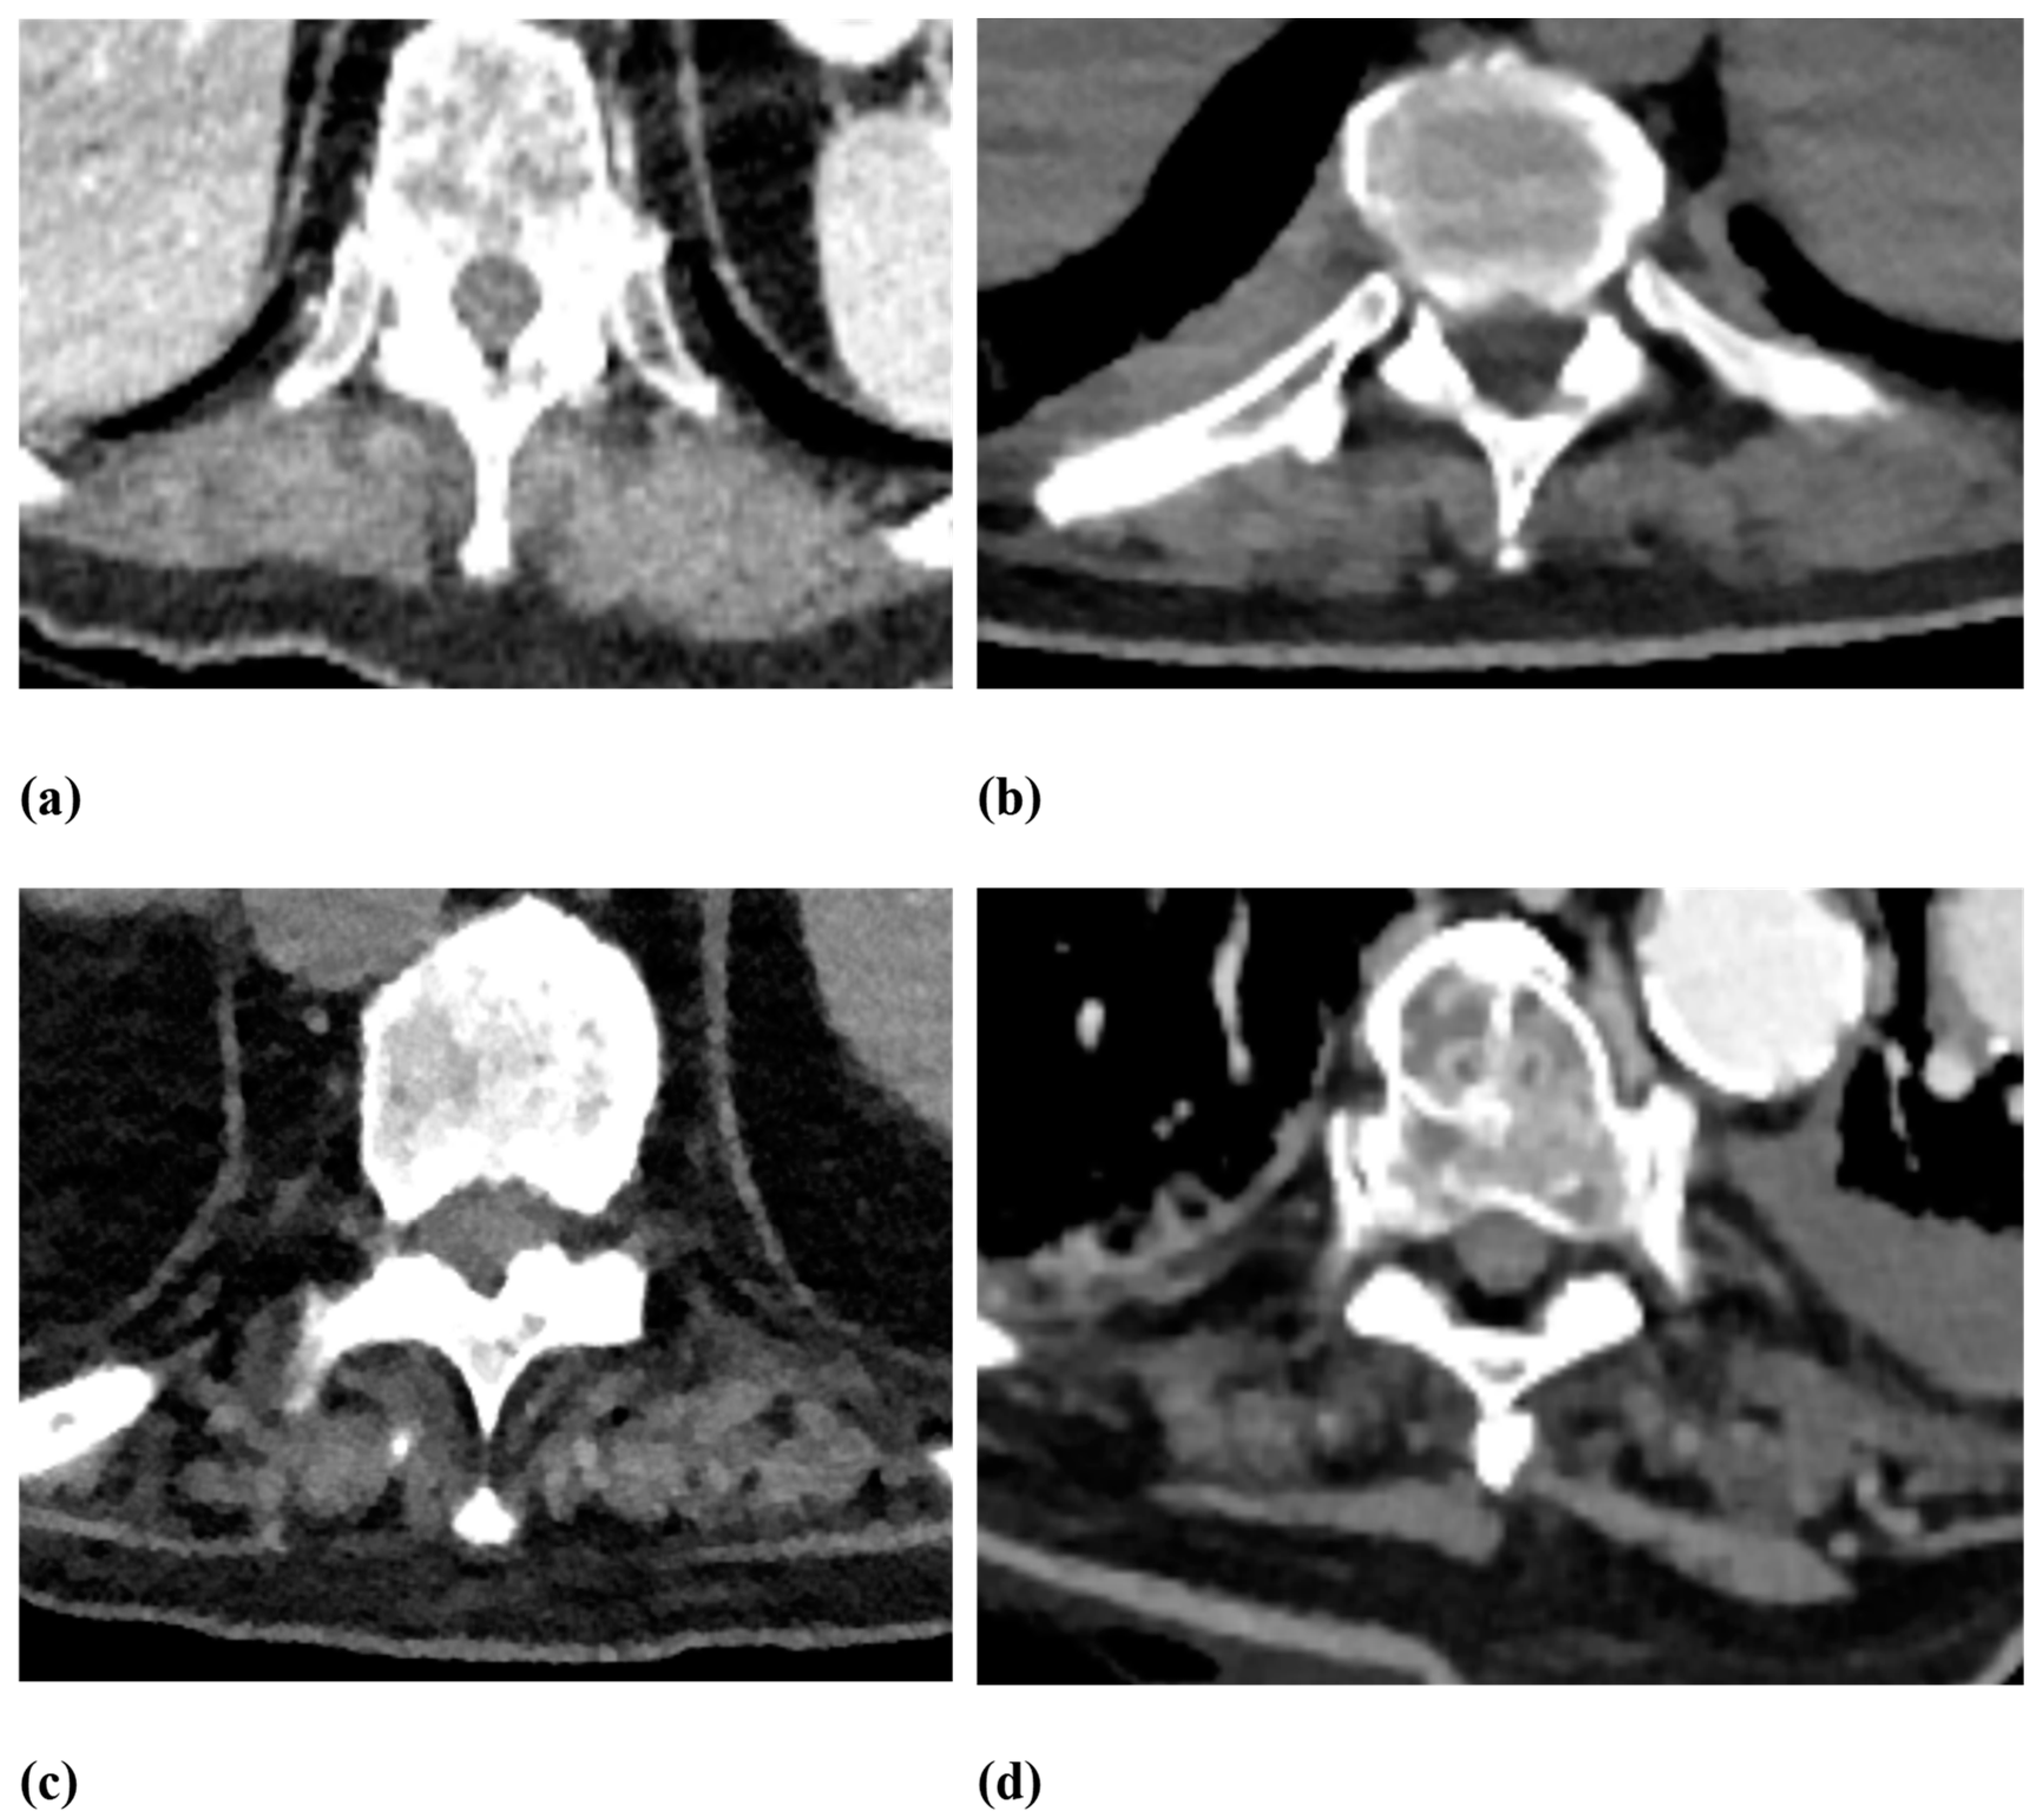

| Vertebral body fractures | Genant Score:

|